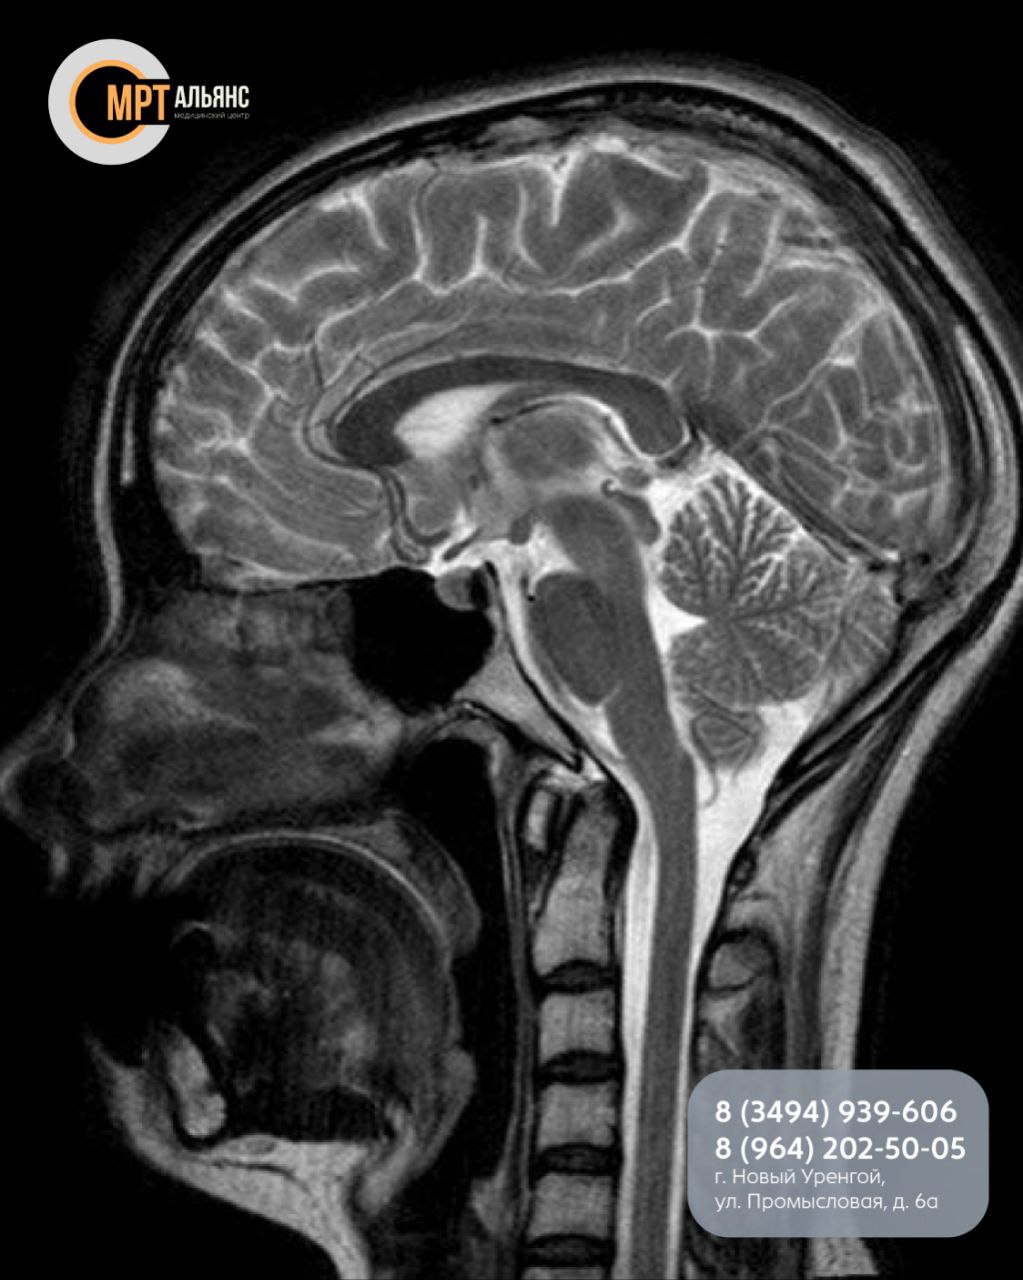

Гипофиз — это крошечная, но могущественная железа, дирижирующая гормональной системой. Сбои в ее работе отражаются на всем.

Когда стоит сделать МРТ гипофиза? Пройдите обследование, если вас беспокоят:

· Необъяснимые головные боли

· Резкое ухудшение зрения, выпадение полей

· Нарушения роста (у детей или взрослых)

· Беспричинное изменение веса

· Сбои менструального цикла или проблемы с зачатием

· Эректильная дисфункция

· Сильная жажда и обильное мочевыделение

· Резкие изменения состояния кожи и волос

· Повышенная утомляемость и скачки давления

Важно знать перед записью: Исследование имеет ряд ограничений. Основные противопоказания — наличие кардиостимуляторов, металлических имплантов и татуировок с металлическими красками. Контрастное усиление не проводится при аллергии на компоненты, беременности и почечной недостаточности.

Точное заключение и возможность проведения МРТ в сложных случаях определяет наш специалист.